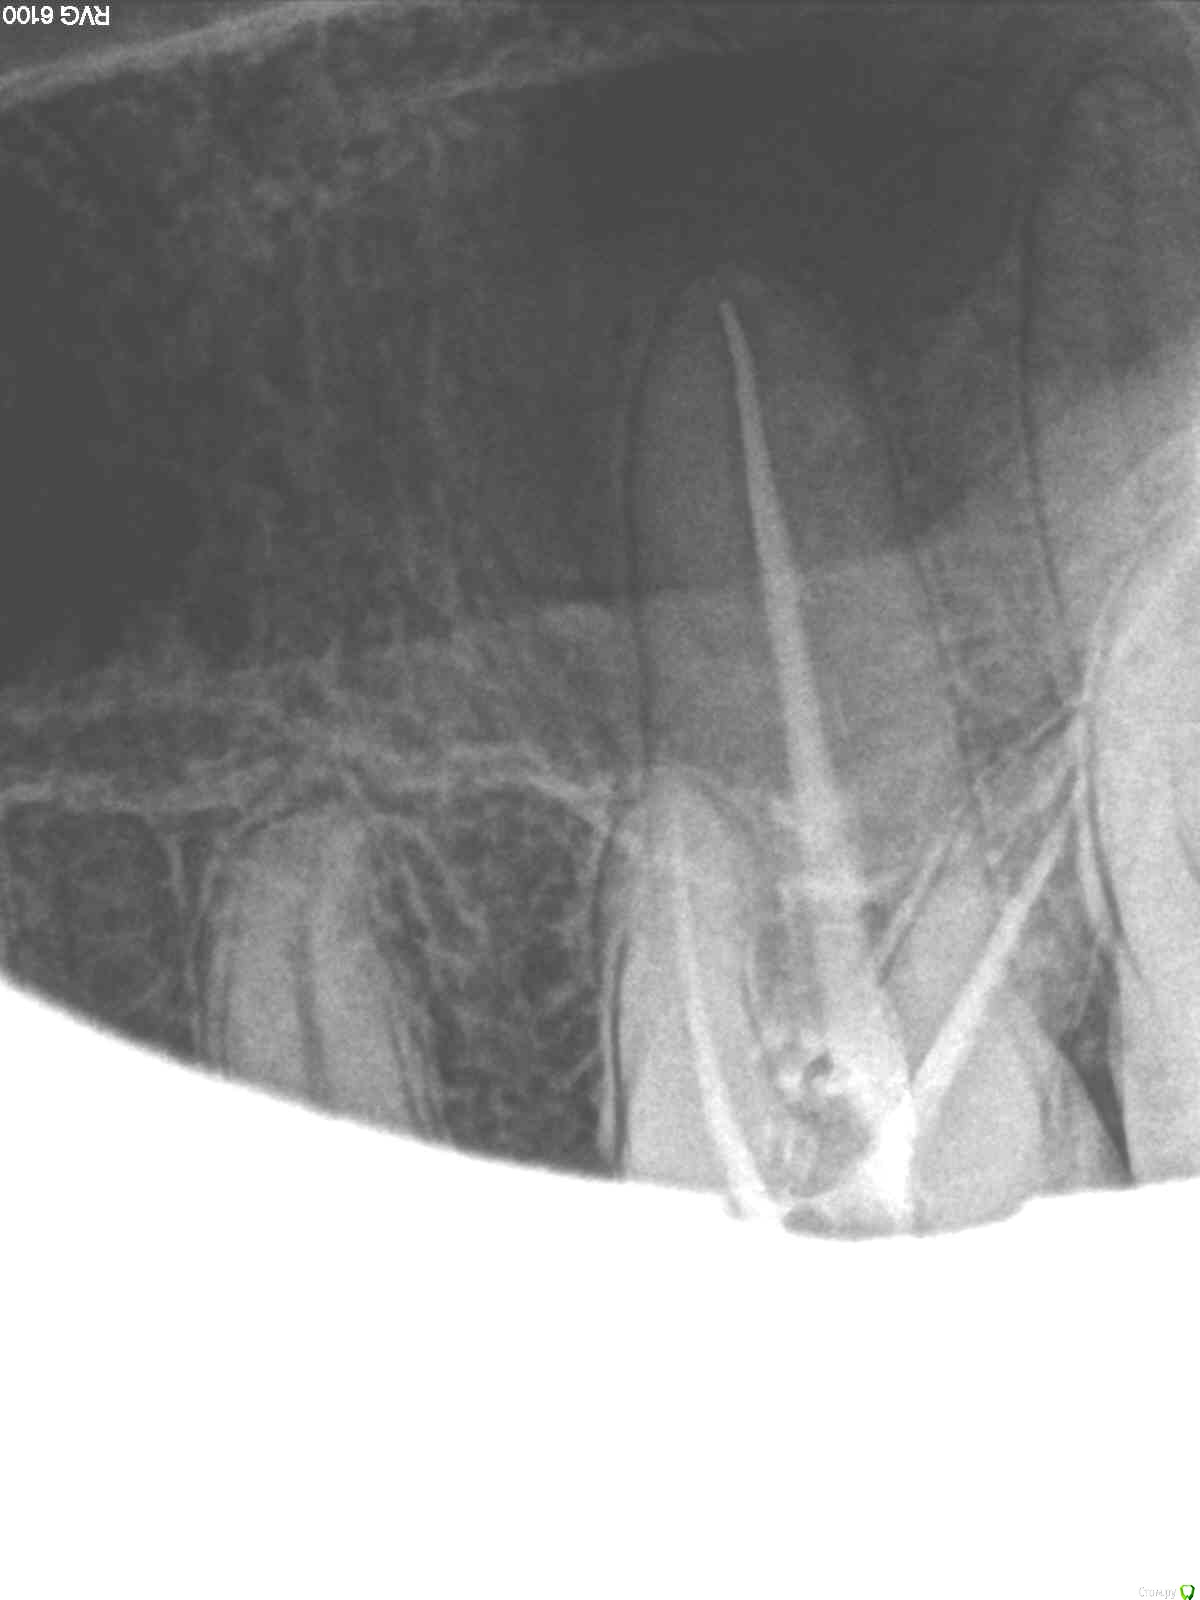

SolnceSamara Опубликовано 24 октября, 2015 Поделиться Опубликовано 24 октября, 2015 почернела старая пломба в давно пролеченной шестерке (сверху). Врач заменила пломбу но зуб болел при надавливании, заменили пломбу повторно-все равно осталась боль, сменила врача-снова сменили пломбу-снова болит, решили депульпировать-снова вынули пломбу, поставили временную-неделю проходила с временной-через неделю окончательно депульпировали, поставили постоянную. Сначало поболело 3 дня, и вроде прошло, хотя остался дискомфорт при надавливании. Прошло 3 недели, боль усилилась, теперь болит не только при надавливании иногда просто звеняще-ноющее ощущение нарастает. Пью нимесил. Посоветуйте что делать-что не так? Снимки прилагаю-делали на протяжении всйх операций (до и после).Разьяснение по снимкам :R1-29/08/15R2,R3-25/09/15R4-R7-28/09/15 Ссылка на комментарий

red_butler Опубликовано 24 октября, 2015 Поделиться Опубликовано 24 октября, 2015 Коллеги поправят, но выглядит как пломбирование одиночным штифтом. Возможно пропущен четвертый канал. Нужна ревизия корневых каналов. 2 Ссылка на комментарий

DmitrySH Опубликовано 24 октября, 2015 Поделиться Опубликовано 24 октября, 2015 Коллеги поправят, но выглядит как пломбирование одиночным штифтом. Возможно пропущен четвертый канал. Нужна ревизия корневых каналов. Все верно. Ссылка на комментарий